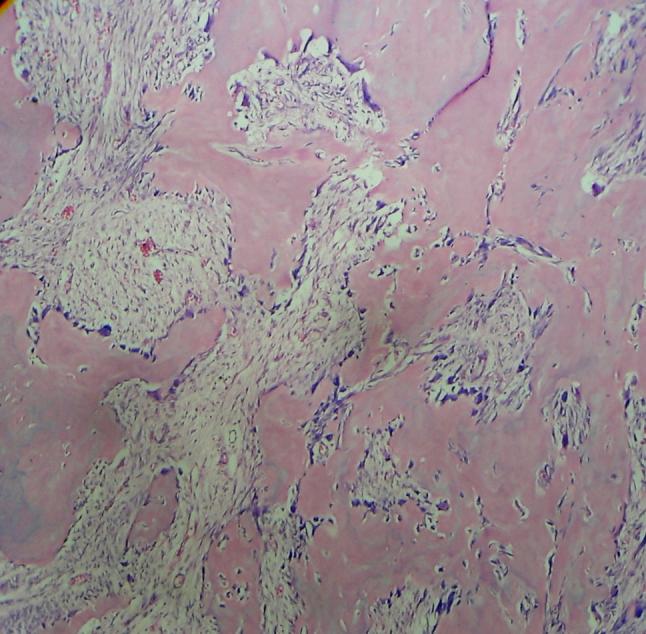

下颌骨骨样骨瘤:一例病例报告并文献复习

Osteoid osteoma of the mandible: A case report with review of the literature.

Osteoid osteoma is a benign skeletal neoplasm most frequently observed in young individuals. The tumor most commonly occurs in the femur, the tibia, and the phalanges; however, jaw lesions are very rare. Herein, we report a rare case of osteoid osteoma that presented in the mandible of a 20-year-old boy. This report also reviews the cases of osteoid osteomas of the jaws that have been reported in the English literature so far.

摘要

骨样骨瘤是一种良性骨肿瘤,最常见于年轻人。该肿瘤最常发生于股骨、胫骨和指骨;然而,颌骨病变非常罕见。在此,我们报告一例罕见的骨样骨瘤病例,发生在一名20岁男孩的下颌骨。本报告还回顾了迄今为止英文文献中报道的颌骨骨样骨瘤病例。